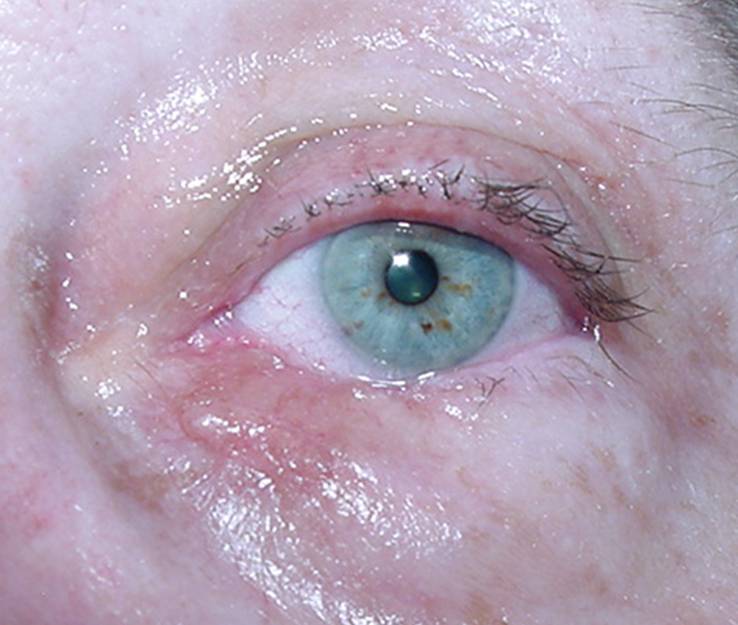

| Fig.3.: Defecto de un 35 % del párpado inferior. El defecto parece más grande por la tracción muscular en los restos del párpado. |

Fig.4: Se ha cortado el ligamento palpebral lateral (cantolísis) para poder transponer el resto del párpado lateral y cerrar el defecto directamente. |